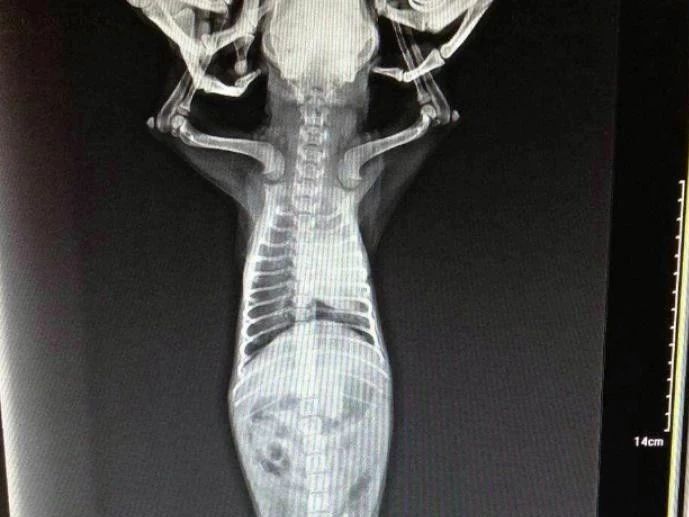

当然,由于心丝虫生活周期的特点,6个月以下的幼犬血液中是观察不到微丝蚴的。除此之外,胸腔X光、心脏B超、心电图都可以辅助判断病情。

Blood samples from dogs were collected for microscopic examination for the presence of microfilariasis. The incidence of filariasis and the number of possible infections of adults were determined by the number of microfilariasis. In addition, chest X - ray, heart B - mode ultrasound, electrocardiogram can help judge the condition.